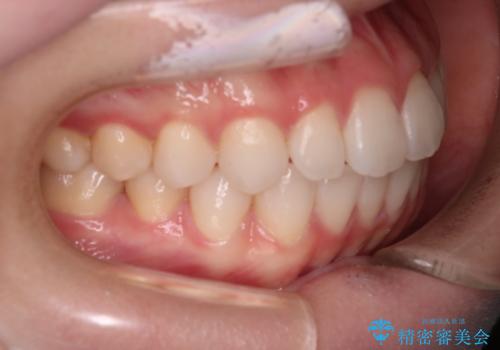

【審美装置】前歯で噛めない!抜歯しないで治したい

- 前歯の捻転とかみ合わせを主訴に来院されました。今回は抜歯をせずにIPRを実施し、並べる計画を立てました。

ワイヤー矯正を行いながら、顎間ゴムを患者さまにご協力していただき、短い期間で終了できました。